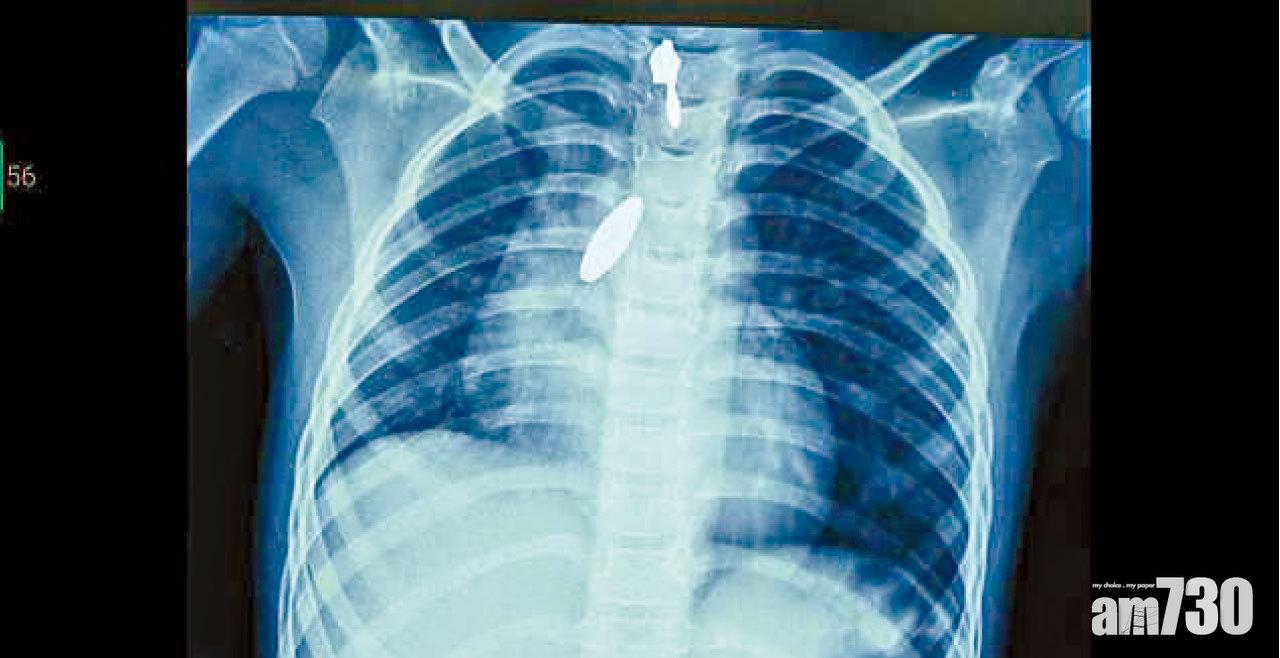

肺卡磁鐵 強力攝石吸出

以毒攻毒,以磁吸磁。印度班加羅爾一名9歲女童玩耍時意外吸入一粒磁鐵,送院救治後,醫生試圖用支氣管鏡檢查儀,夾出附在肺部的1吋長異物,但太滑無法夾穩。最後毋須動手術即將它吸入氣管、再輕易從口而出──妙法是一塊超強力磁石。  (互聯網)